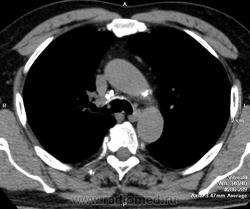

А что по медиальной стенке промежуточного бронха на второй серии сканов?

Вношу ясность: тут два исследования - первое исследование сделано в понедельник, второе во вторник - в просвете бронха имеет место что то симулирующее tr, что было на верхней стенке, а затем переместилось на нижнюю за сутки - слизь.

Для спокойствия надо через неделю еще КТ сделать ))))), да и сомнительно, чо при горизонтальном положении больного слизь имеет такую форму...